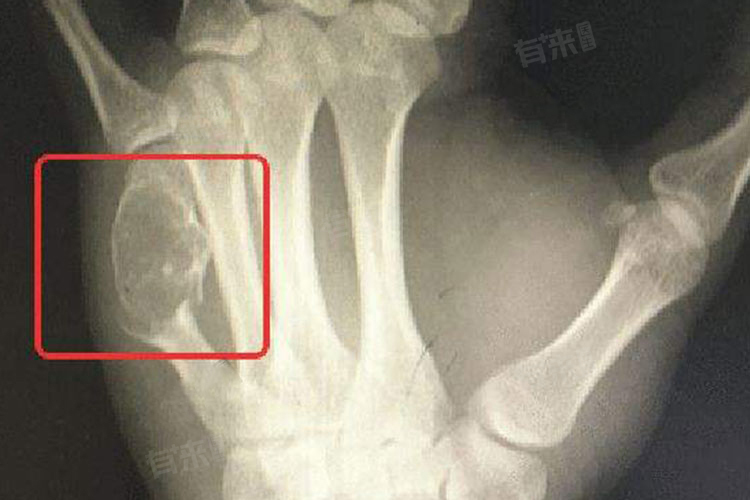

- 在病情严重时,患者还可能发生病理性骨折,即因骨骼病变而导致的骨折。全身症状也是骨癌的一种表现,如发热、体重下降、疲劳和活动能力下降等。这些症状不仅影响患者的生活质量,还可能进一步加重患者的病情。